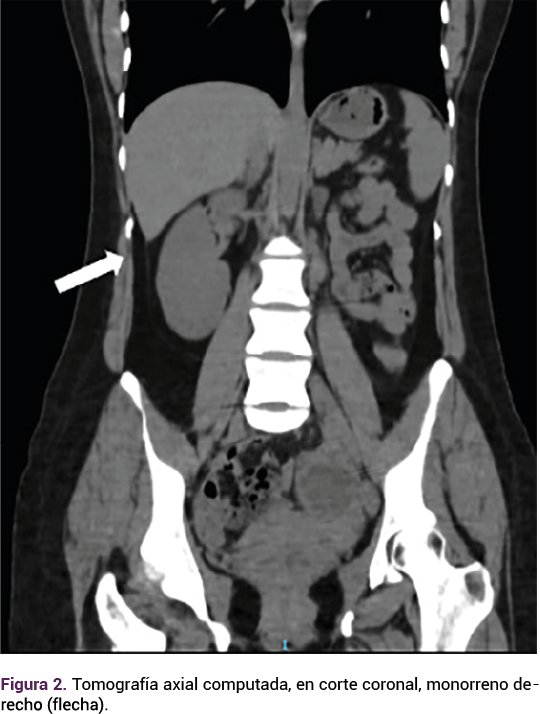

Gracias al protocolo institucional de estudio de la infertilidad, la paciente logró el embarazo espontáneo que culminó en anembriónico. Con ultrasonido endovaginal se diagnosticó la alteración mülleriana y una vez resuelta con legrado uterino instrumentado se envió a la consulta especializada en fertilidad. El hallazgo de la resonancia fue el útero didelfo con vagina doble y hematocolpos izquierdo. Figura 1

Figura 1.

El síndrome de OHVIRA es una anomalía mülleriana poco común que se origina debido al desarrollo anormal del aparato reproductor. Durante la embriogénesis, el desarrollo normal de éste se inicia a las 6 semanas. Los conductos de Müller, que dan origen a las trompas de Falopio, el útero y la parte superior de la vagina cruzan los conductos de Wolff y migran hacia la línea media para fusionarse y formar el primordio úterovaginal.5 Después de la reabsorción del tabique, en el primordio úterovaginal, se desarrolla solo un conducto. En el síndrome de OHVIRA el desarrollo anormal del conducto de Wolff impide el cruce y posterior fusión de los conductos de Müller, lo que da lugar a dos cuernos uterinos, dos cuellos uterinos y dos hemivaginas.6

La falta de fusión parcial entre el conducto paramesonéfrico y el bulbo sinovaginal da lugar a la formación del tabique vaginal, que puede ubicarse en la parte superior (46%), media (40%) o inferior de la vagina (14%).6 Los conductos de Wolff dan origen a los riñones, y son inductores de la fusión correcta de los conductos müllerianos. Una alteración en el desarrollo de la porción caudal, de uno de los conductos de Wolff, puede originar agenesia renal unilateral, asociada con hemivagina obstruida ipsilateral.5,7 Por lo general, se diagnostica en niñas después de la pubertad, por la acumulación de sangre en el útero obstruido.5 Se han diagnosticado casos excepcionales en el periodo neonatal, mientras que otros casos pueden diagnosticarse en la primera infancia, secundario a problemas renales concurrentes.8 En la paciente del caso el diagnóstico se estableció a los 33 años, y posterior al estudio de pareja con infertilidad.